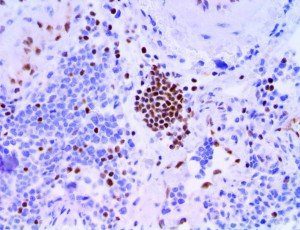

It is the ICU physician who is most likely to witness one of the deadliest manifestations of the abnormal immunological response, the cytokine storm syndrome (CSS). This response is also referred to by some as the cytokine release syndrome (CRS). CSS is characterized by continuous activation and expansion of macrophage and lymphocyte populations, which secrete large amounts of cytokines, causing the cytokine storm. This massive cytokine release is akin to hemophagocytic lymphohistiocytosis (HLH) disease, a syndrome characterized by initial unchecked and persistent activation of cytotoxic T lymphocytes and NK cells.

Clinical and laboratory manifestations of HLH include fever, enlarged liver and/or spleen, neurologic dysfunction, coagulopathy, liver dysfunction, cytopenias (i.e., low levels of erythrocytes, leukocytes, and/or platelets), hypertriglyceridemia, hyperferritinemia, hemophagocytosis, and eventually diminished NK cell activity as the immune system becomes progressively paralyzed. HLH can be familial (primary HLH) or secondary to another disease process (sHLH), such as rheumatic disease, in which it is referred to as macrophage activation syndrome (MAS, characterized by elevated ferritin).